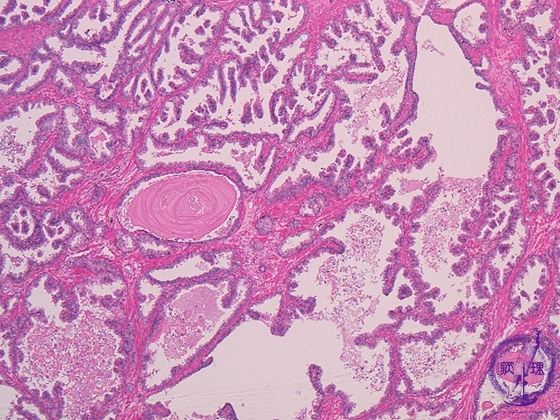

Histology (HE stain, low power): Glands with serrated epithelium proliferated in nodular pattern (glandular hyperplasia). In some cases, nodular hyperplasia of interstitial fibromuscular tissue (stromal hyperplasia) could be predominant, in other cases, both type of hyperplasia can be identified.